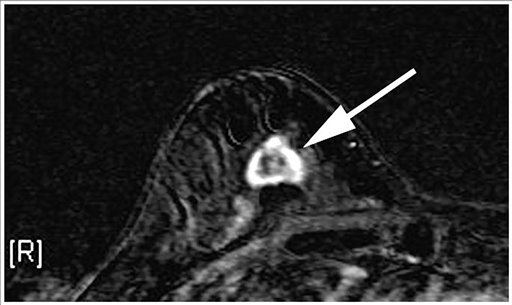

The treatment builds on Herceptin, the first gene-targeted therapy for breast cancer. It is used for about 20 percent of patients whose tumors overproduce a certain protein.

Researchers combined Herceptin with a chemotherapy so toxic that it can’t be given by itself, plus a chemical to keep the two linked until they reach a cancer cell where the poison can be released to kill it.

This double weapon, called T-DM1, is the “smart bomb,” although it’s actually not all that smart — Herceptin isn’t a homing device, just a substance that binds to breast cancer cells once it encounters them.

“I call it ‘Herceptin-plus,'” she said. Scans every six weeks show “everything is still shrinking or stable,” she said. “Right now, I’m feeling pretty good about it. The only way I’d feel a little better is if it took care of everything, but I’ll take what I can get.”